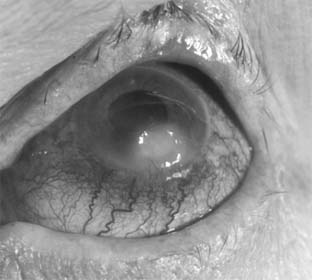

Pseudomonas corneal ulcer begins as a gray or yellow infiltrate at the site of a break in the corneal epithelium (Figure 6-2). Severe pain usually accompanies it. The lesion tends to spread rapidly in all directions because of the proteolytic enzymes produced by the organisms. Although superficial at first, the ulcer may affect the entire cornea. There is often a large hypopyon that tends to increase in size as the ulcer progresses. The infiltrate and exudate may have a bluish-green color. This is due to a pigment produced by the organism and is pathognomonic of P aeruginosa infection.

Figure 6-2

Figure 6-2: Pseudomonsa ulcer related to 24-hour contact lens wear.

Pseudomonas is a common cause of bacterial corneal ulcers. Cases of Pseudomonas corneal ulcer may follow minor corneal abrasion or the use of soft contact lenses-especially extended wear lenses. Corneal ulcers caused by this organism can vary from quite benign to devastating. The organism has been shown to adhere to the surface of soft contact lenses. Some cases have been reported following the use of contaminated fluorescein solution or eye drops. It is mandatory that the clinician use sterile medications and sterile technique when caring for patients with corneal injuries.

Scrapings from the ulcer may contain long, thin gram-negative rods that are often few in number. Drugs recommended for use in treatment are listed in Tables 6-2 and 6-3.